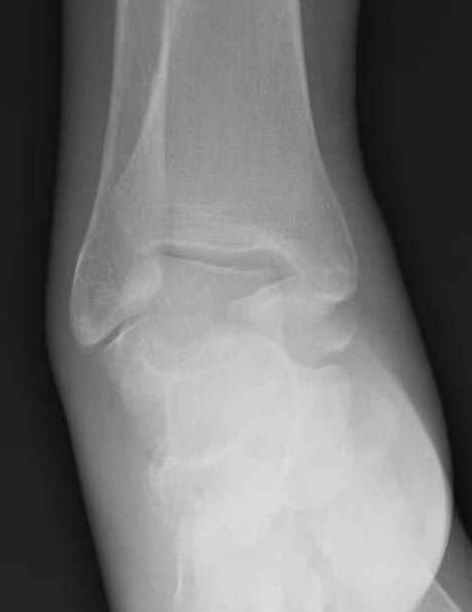

из

Уважаемые участники русского Ортофорума, поздравляю всех со всеми прошедшими праздниками: Новым годом, Рождеством, Hanukkah, Kwanzaa, желаю участникам всего наилучшего и здоровья. Повреждение таранной кости. Больной 81г автоавария, повреждение таранной кости, здесь снимки.

Какие рекомендации? Djoldas Kuldjanov, MD Department of Orthopedic Surgery St. Louis University Medical Center